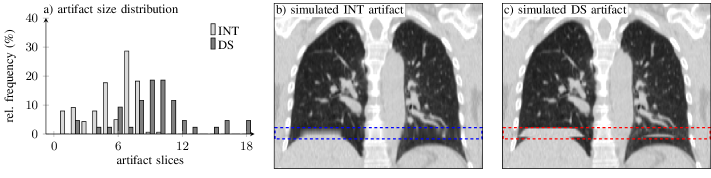

Refer to caption

Figure 3: a) INT and DS artifact size distributions for a subset of the in-house data set. b) Illustration of simulated INT (highlighted by blue box) and c) DS (red box) artifacts.

The artifact type-specific models presented in section II-C were trained and tested using the aforementioned data split. Based on an initial evaluation of the in-house data set, we randomly inserted up to three (95th percentile of the number of artifacts per 4D CT phase image) DS or INT artifacts into a single 4D CT phase image according to section II-B. Simulated artifacts are illustrated in fig. 3 b and c. INT artifacts were simulated for axial slices along the entire z𝑧z-range of the lung bounding box; DS artifacts were only generated in the lower third of the bounding box as they usually occur in areas of more pronounced structure motion, i.e., in lower parts of the lung. The artifact size was sampled from a uniform distribution in the range of [2,18]218[2,18] slices (see fig. 3 a). All available 4D CT phase images were used for the artifact simulation. The model performance was evaluated using standard accuracy (patient-wise evaluation, weighted by number of artifact slices) and AUC-ROC measures on all 4D CT phase images in the validation set.